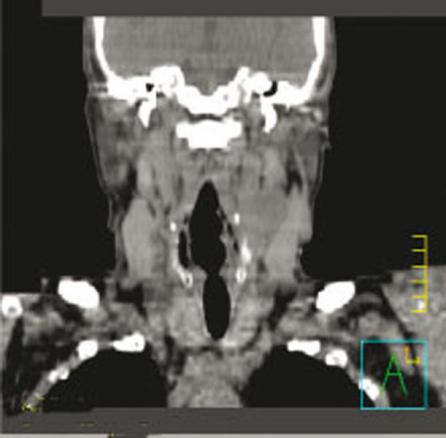

TDM simple : face. Carcinome épidermoïde du sinus piriforme gauche avec une adénopathie tumorale nécrosée sous-digastrique gauche.